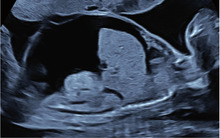

Abb. 4 Sonographischer Befund eines Feten in SSW 19 mit B19V-bedingtem Hydrops fetalis (mit freundlicher Genehmigung von Prof. Dr. med. Karl Oliver Kagan, Universitätsfrauenklinik Tübingen)

Bei Schwangeren verläuft die Infektion nicht schwerer als bei Nichtschwangeren. Die intrauterine Transmissionsrate beträgt etwa 30-50%, die Mehrzahl der fetalen Infektionen hat aber keine negativen Auswirkungen auf das ungeborene Kind. Weniger als 10% der mütterlichen B19V-Infektionen in den ersten 20 Schwangerschaftswochen führen zu fetalen Komplikationen, danach ist diese Rate noch deutlich geringer (<1-2%). Die Häufigkeit eines Hydrops fetalis nach maternaler B19V-Infektion beträgt über den gesamten Zeitraum der Schwangerschaft 3-4%, das Risiko von Abort oder intrauterinem Fruchttod liegt bei 3-14% und ist hier nach mütterlicher Infektion im 1. Trimenon am größten. Das zeitliche Intervall zwischen Infektion der Mutter und dem Auftreten von Komplikationen beim Ungeborenen beträgt in 75-90% der Fälle weniger als 8 Wochen und in weniger als 5% der Fälle mehr als 12 Wochen. Am häufigsten werden fetale Komplikationen zwischen der 10. und 24. SSW festgestellt (Abb. 4).